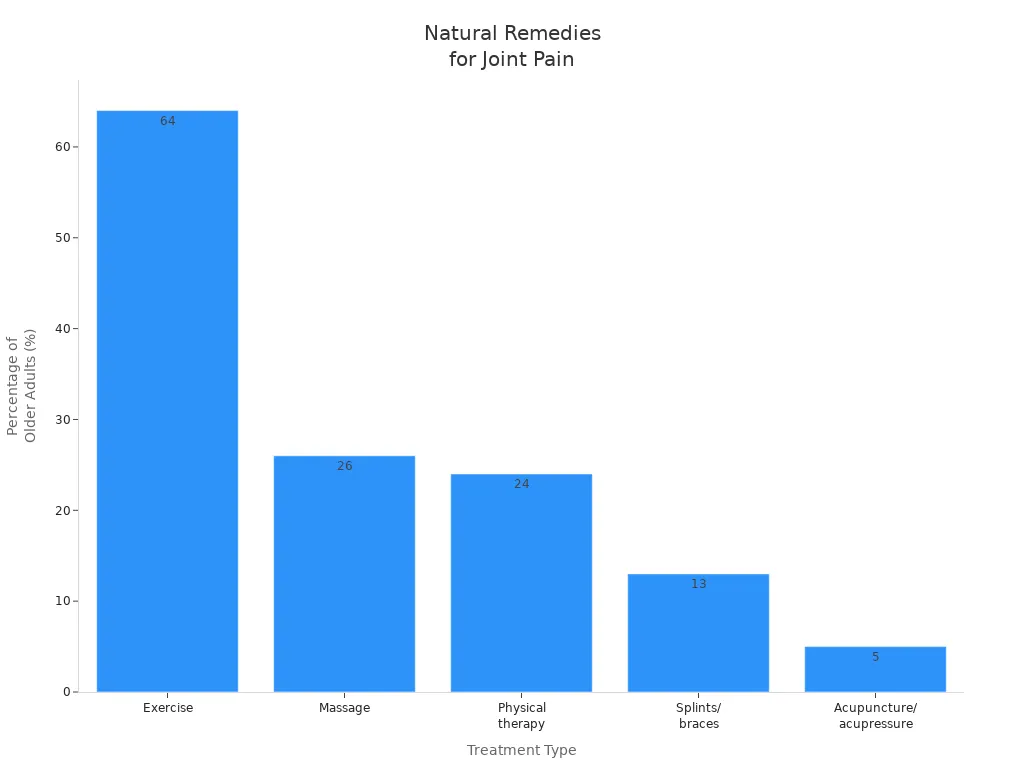

Breakdown of non-pharmacologic treatments: | Exercise (64%), Massage (26%), Physical therapy (24%), Splints/braces (13%), Acupuncture/acupressure (5%) |